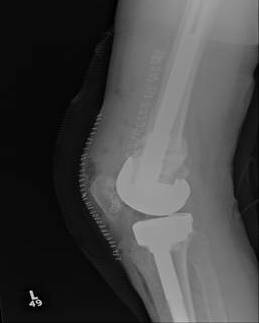

TKR Intraoperative condylar fractureTKR Condylar Fracture Lateral